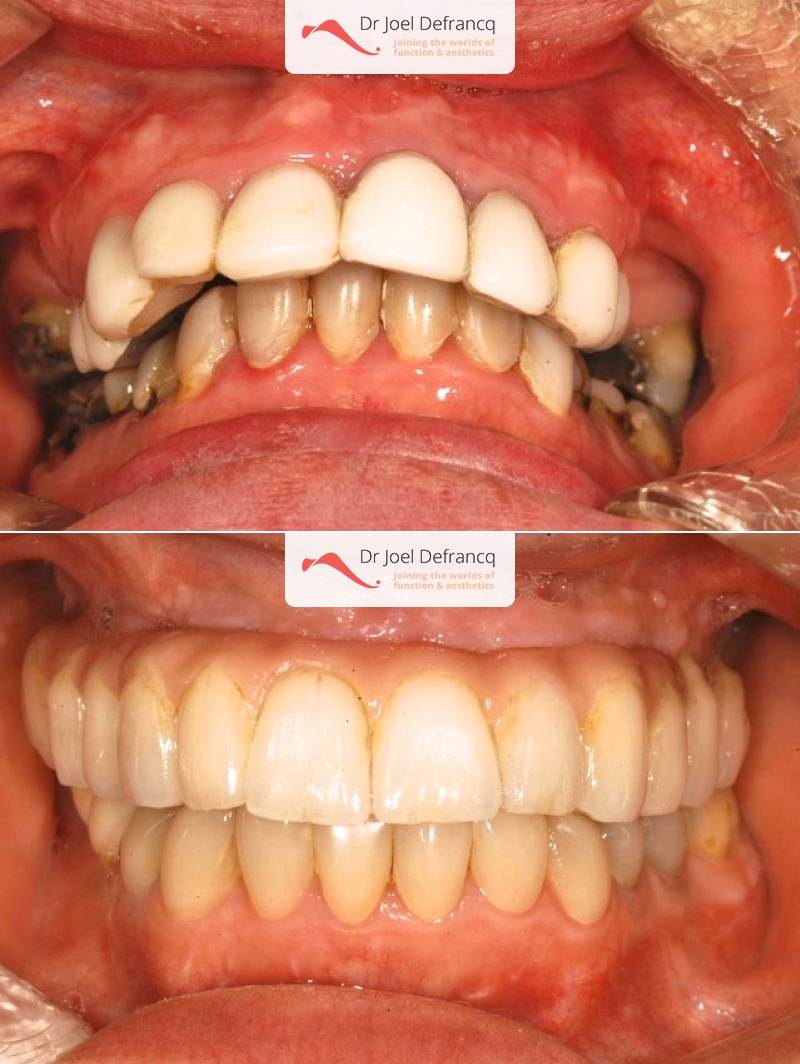

Vicky: Tandvlees lach. Kaakchirurgie met implanten.

Diagnose van het gezicht

- Te kleine onderkaak (Overbeet)

- Te lange bovenkaak

Dentale diagnose

- Klasse II divisie 1

Behandeling tandheelkundige implantaten

- Vaste tanden op implantaten (bovenkaak)